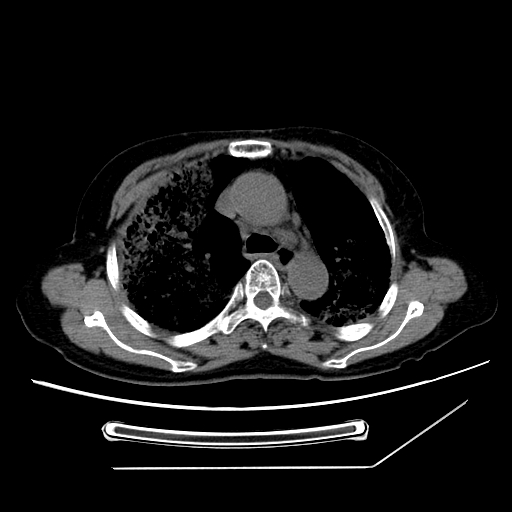

标题: CT25393:病人45岁,咳嗽,吐黄痰带血丝,发热,胸闷月余 [打印本页]

标题: CT25393:病人45岁,咳嗽,吐黄痰带血丝,发热,胸闷月余

1、左肺中央型肺癌并双肺弥漫性转移   2、双肺部感染    3、肺大泡     4、左侧胸腔积液

双侧肺弥漫性病变,可见“空泡征”及“蜂窝征”,考虑肺泡癌可能性大,左侧胸腔积液,考虑胸膜受累可能!

1)不排除肺泡癌可能。2)左侧胸腔积液。